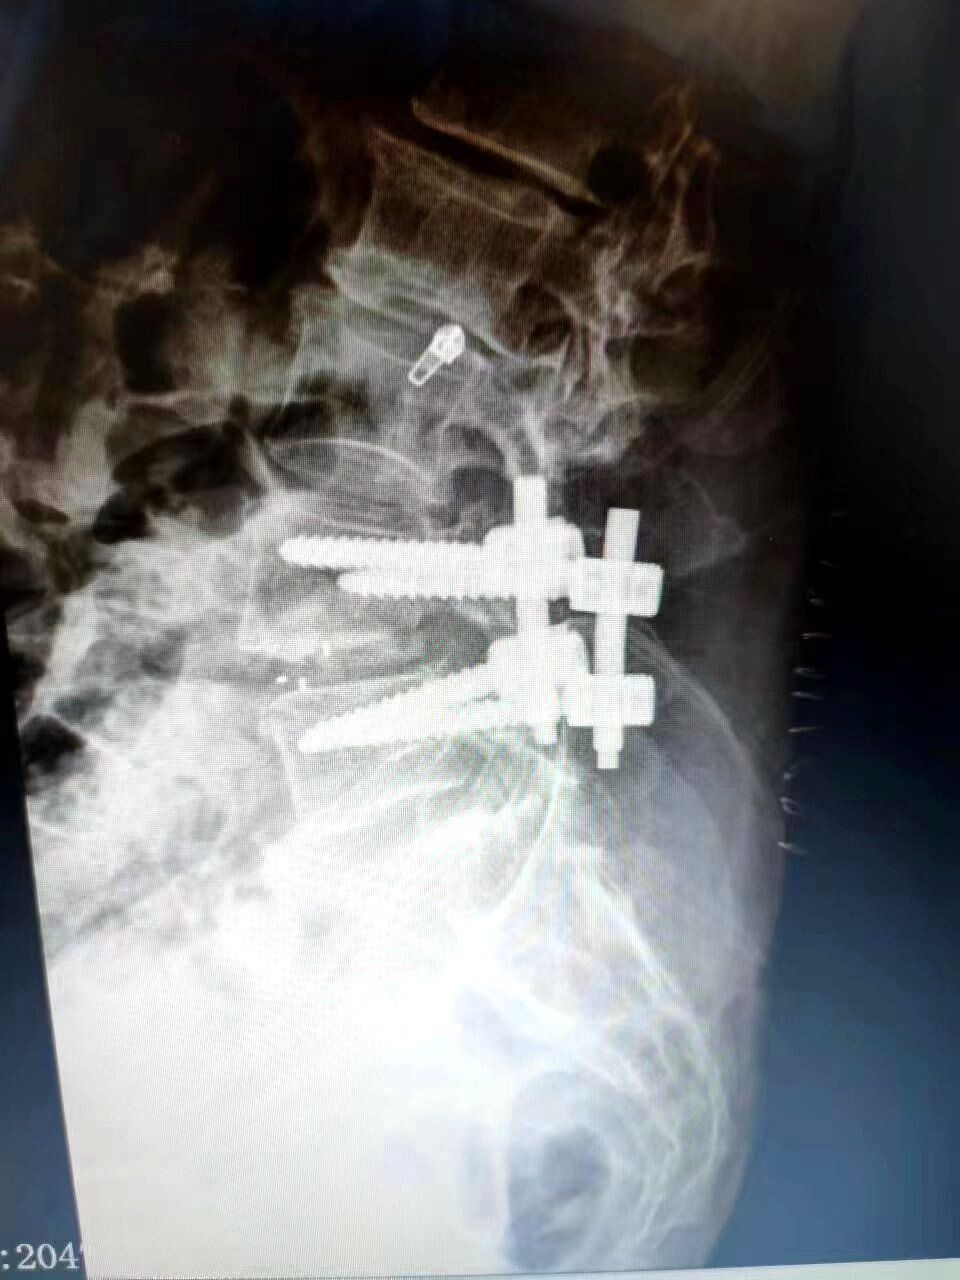

神經(jīng)外科副主任劉沛濤接診后,經(jīng)過詳細輔助檢查,診斷為L5神經(jīng)根病、腰椎滑脫、腰椎間盤突出癥,需手術治療。考慮到患者年齡大、體質差,傳統(tǒng)手術方式切口大,術后臥床時間長,顯微鏡下微創(chuàng)手術操作更精細,治療更精準,對患者機體損傷小,是目前治療脊柱脊髓疾病的首選方案,但微創(chuàng)手術對手術適應癥及手術技術的要求更高,因此科主任喬景尊組織科室團隊反復討論手術方案,進行充分術前評估后,劉沛濤及科室團隊在麻醉科通力合作下,采取顯微鏡下L5神經(jīng)根減壓+腰間盤切除+椎間植骨融合+釘棒內(nèi)固術,經(jīng)過2個多小時的謹慎、精細操作,順利完成了手術,患者安全返回病房。

神經(jīng)外科副主任劉沛濤介紹,神經(jīng)根病變的原因有椎間盤突出、椎管狹窄、椎體滑脫等,主要表現(xiàn)是腰痛、腿痛,傳統(tǒng)治療對于輕癥患者一般選擇藥物鎮(zhèn)痛、康復理療等方式,藥物及理療仍不能緩解的患者首選手術治療。傳統(tǒng)手術創(chuàng)傷大、出血量多、恢復慢,此次開展的顯微鏡下神經(jīng)根減壓術,利用人體腰椎自然解剖間隙,到達病變部位進行減壓,從而解除神經(jīng)根受壓,圓滿達到了治療目的。(通訊員:尹紅婭 李忠麗)